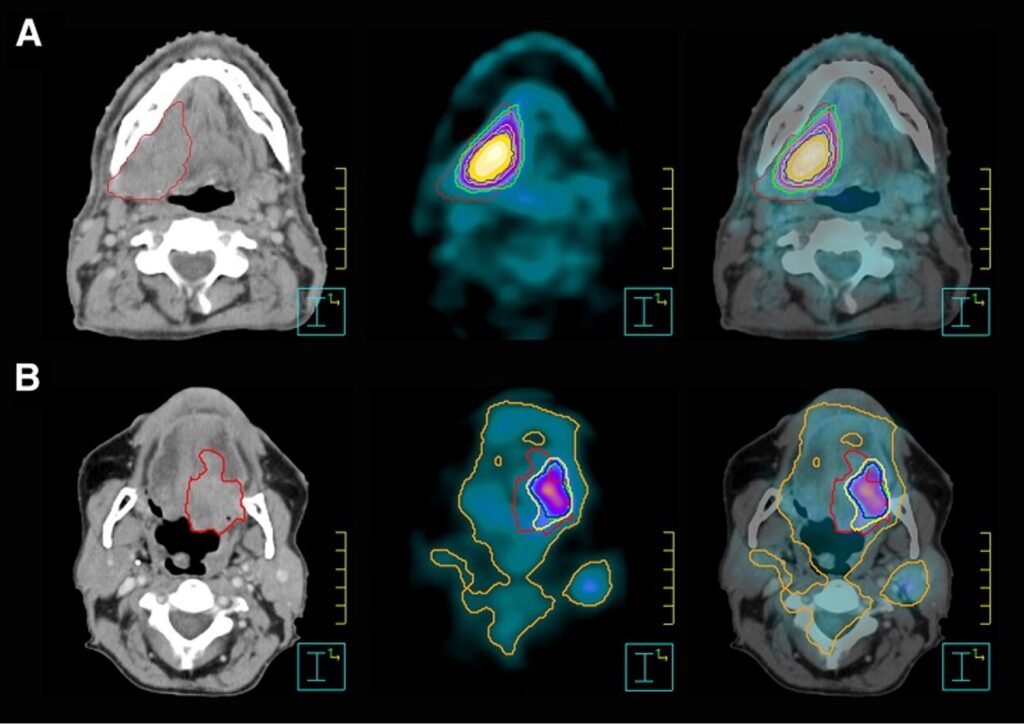

Teşhis, hastanın semptomlarına göre fiziksel muayene, endoskopi, biyopsi, bilgisayarlı tomografi (BT), manyetik rezonans görüntüleme (MRG) veya PET taraması gibi görüntüleme yöntemleriyle yapılır.

Tedavi kanserin evresine, tipine ve hastanın genel sağlık durumuna bağlı olarak değişir. Genellikle cerrahi, radyoterapi, kemoterapi veya immünoterapi kombinasyonları kullanılır. Erken teşhis edilen vakalar, daha az invaziv tedavi yöntemleriyle tedavi edilebilir.